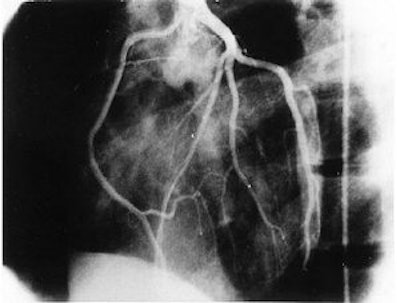

![]() |

| The same 17-year-old asymptomatic basketball player. Coronary artery angiography in the left oblique anterior view. Selective injection of contrast medium in the left sinus of the Valsalva confirms that the right coronary artery originates from the left sinus just anterior to the left coronary ostium. Zeppilli P, dello Russo A, Santini C, Palmieri V, Natale L, Giordano A, Frustaci A, "In vivo detection of coronary artery anomalies in asymptomatic athletes by echocardiographic screening" (Chest, 1998 Jul;114(1):89-93). |